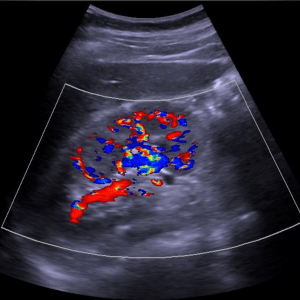

Actualmente trabajo como profesionista independiente. Realizo estudios de ultrasonido de todo tipo: abdominal, renal, hepatobiliar, ginecológico, prostático, tiroideo, inguinal, escrotal, así como estudios de arterias y venas (Doopler color y espectral) en brazos, piernas y cualquier otro órgano del cuerpo. En caso de indicación médica puedo realizar biopsias del cuello (tiroides y ganglios), abdomen (hígado, riñón) o próstata, así como extraer líquido acumulado en la pleura (membrana que recubre los pulmones) y en el abdomen, entre otros.